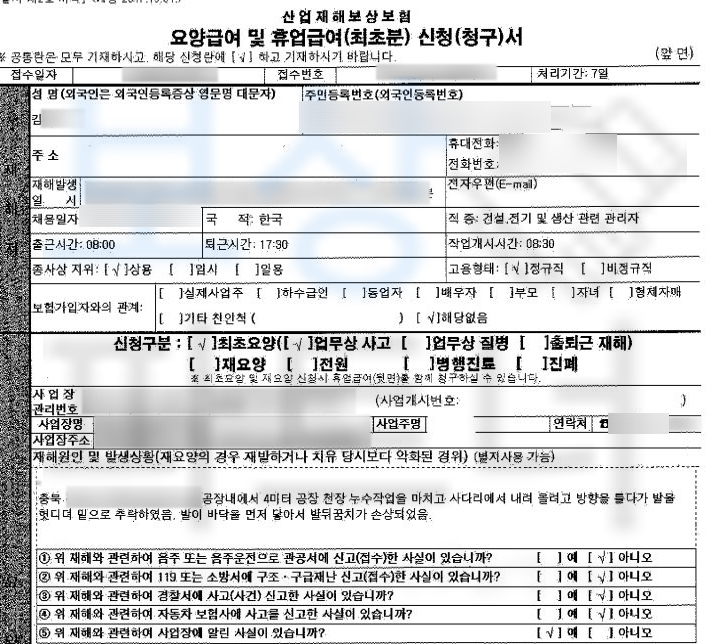

청주시 거주하시는 김@@님은 공장의 천장 누수 작업을 마치고 사다리에서 내려 가기 위해 방향을 틀던 중 발을 헛디뎌 4미터 높이에서 추락하였으며 발이 바닥에 먼저 닿아 발뒤꿈치 골절 즉 종골골절 진단을 받았습니다.

종골의 골절, 폐쇄성 S9200 진단을 받았습니다. 위 병명으로 김@@님은 관혈적 정복 후 금속 고정술 시행받았고 10주간 석고 고정 진단을 받았습니다. 먼저 일하다 다친 사고이기에 의무 가입인 산재 보험에서 치료비와 일을 못하는 기간에 대해 보상을 받을 수 있습니다.

위 실제 작성하신 사례처럼 사고 경위를 그.대.로 적으시고 사고 발생시 바로 산재 신청을 진행하시는 것이 좋습니다. 산재 신청은 개인적으로 혹은 병원 원무과의 도움을 받아 큰 어려움없이 신청하실 수 있습니다.

양발의 장해 인정되어 상향된 산재 **장해등급 11급 **결정되게 되었습니다. **산재 보상금 30,400,480원 **입니다. 아래의 발의 산재 장해등급표 확인해주세요.